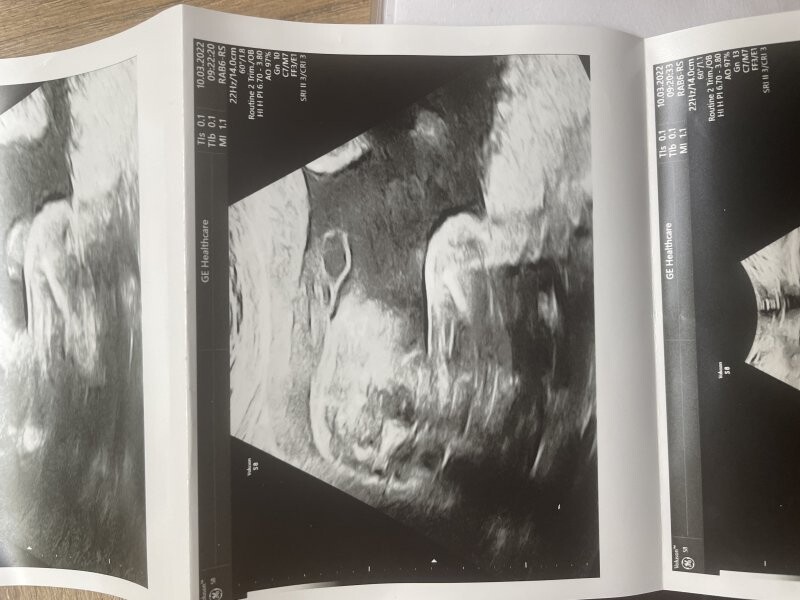

Dobrý den paní doktorko, jsem momentálně těhotná (mám za sebou jedno zamlklé těhotenství, miminko je opravdu vymodlené). První ultrazvuk byl 17.8 (dle ms mělo být 6+3) a pan doktor v CAR vypočítal těhotenství na 6+0 s AS, což není nic zvláštního, protože vzhledem k PCOS mívám ovulaci opravdu později. Vzhledem k tomu, že pracuji v nemocnici a stal se mi tam takový malý úraz (uklouzla jsem) tak se mi hned pan doktor nabídl, že uděláme kontrolní ultrazvuk (tudíž jiný lékař, jiný ultraz.přístroj). Vyděšil mě když těhotenství vypočítal jen na 6+2 místo 7+0 (bylo to po týdnu). Akce srdeční byla stále..jen mám strach, že se opravdu začíná opožďovat ve vývoji a znovu mě potká zamlklé těhotenství. Přikládám foto z obou ultrazvuků. Připadá mi i laickým okem, že embryo rozhodně větší je. Je možné, že to pan doktor špatně změřl? nebo že každý přístroj měří jinak?Děkuji vám !

Dobrý den, teď je otázka, která struktura byla měřená, zda EES (časná délka embrya) - mluvit o CRL je v tomto týdnu brzy.. nebo např. průměr gestačního váčku.. takto se dle fotky momentálně nejeví nic dramaticky špatně, proto bych vyčkala do další kontroly, v těchto nižších týdnech může být ta velikost taková variabilní a nelze pominout i možnost nepřesného měření. Držím palce!